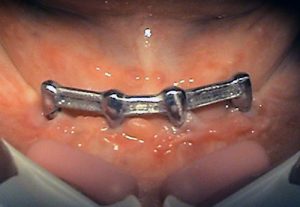

2. PHASE – state before making immediate impressions

3. PHASE – prosthetic fabrication of temporary crown on implant